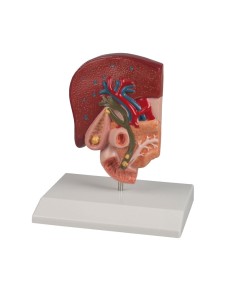

Dal cranio in 22 parti con incastri magnetici ai modelli di colonna vertebrale, da quelli di articolazioni a quelli di cuore, ogni pezzo della nostra collezione è progettato per un’immersione totale nello studio dell’anatomia umana. I nostri modelli, realizzati tramite scansioni di ossa vere, garantiscono un’esperienza tattile autentica e una fedeltà di peso quasi identica agli originali.

Essenziali per studenti e professionisti, i nostri modelli anatomici sono strumenti didattici che permettono di osservare le strutture anatomiche con precisione, eliminando la necessità di dissezioni o studi invasivi. Sono inoltre utili per spiegare ai pazienti le patologie, rendendo la comunicazione più efficace e risparmiando tempo prezioso.